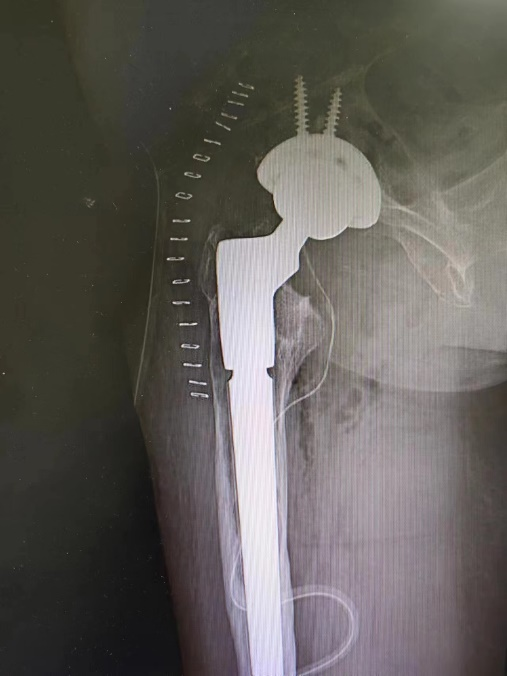

骨科副主任王建伟门诊查体并进行髋 DR 检查发现,患者右侧人工髋关节假体周围骨溶解严重,假体下沉松动。于是骨科团队考虑患者疼痛为人工髋关节置换术后假体松动所致,要想彻底治愈只能做翻修手术。

3 月 8 日,由骨科副主任王建伟主任医师主刀,李延明副主任医师、蔡文龙主治医师、杨志军住院总医师为助手,髋关节翻修手术历时 3 小时按照术前计划顺利完成。术后拍患肢 X 光片提示翻修假体型号、位置良好,完全纠正了术前患肢的短缩畸形。